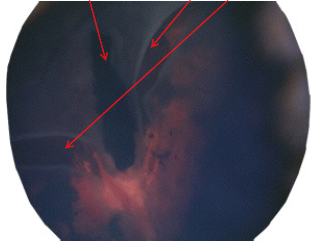

What are the arrows pointing to?

Left = pectin

Right 2 = retinal tear/trauma